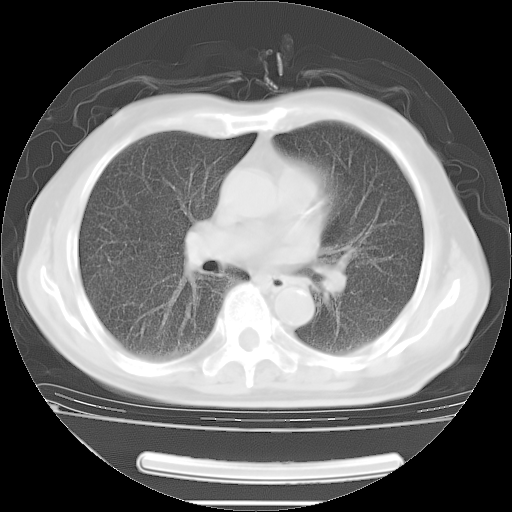

今天复查肺部CT,发现双肺广泛磨玻璃样改变。所以我把3月19日和5月9日相隔50天的肺部CT上传。请大家会诊。

2009年3月19日肺部CT片。

2009年3月19日肺部CT

大致读了系列胸部CT:纵隔窗无明显异常,肺窗:从4、27至今:主要是双肺中下野外带可见毛玻璃样改变,目前处于急性肺泡炎阶段,至于原因考虑1、结替组织或胶原血管性疾病所致?2、恶性疾病如恶组在肺部所致的表现或细支气管肺泡癌?3、药物或其它原因如肺蛋白沉着症所致肺泡炎目前不太可能?总之,明天就去请我院的呼吸科、感染科、血液科和临免专家会诊哈。